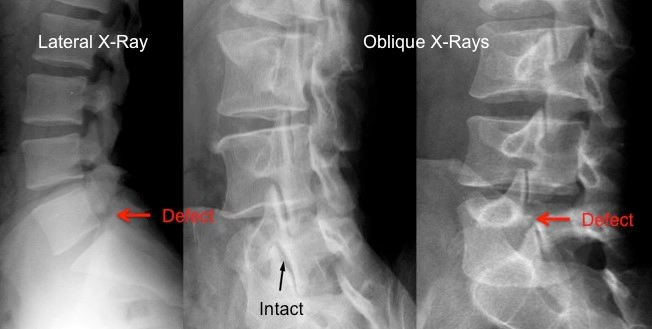

척추분리증은 척추의 일부가 분리되거나 약해지는 상태를 말합니다. 이 조건은 보통 척추의 추궁의 특정부분이 결손되거나 분리되는 데 관련되며, 이는 척추를 안정시키는 데 중요한 구조물입니다. 이것은 가장 흔하게는 척추의 하부인 요추 부분에서 발생합니다.